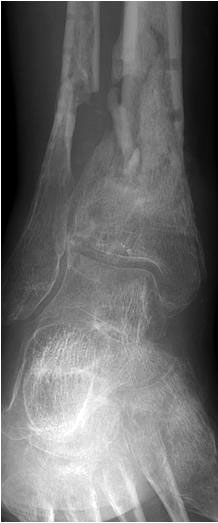

• Revision einer gescheiterten Fusion des OSG/ USG (Abbildung 3, Abbildung 4).

• Pseudarthrosen (Abbildung 5, Abbildung 6).